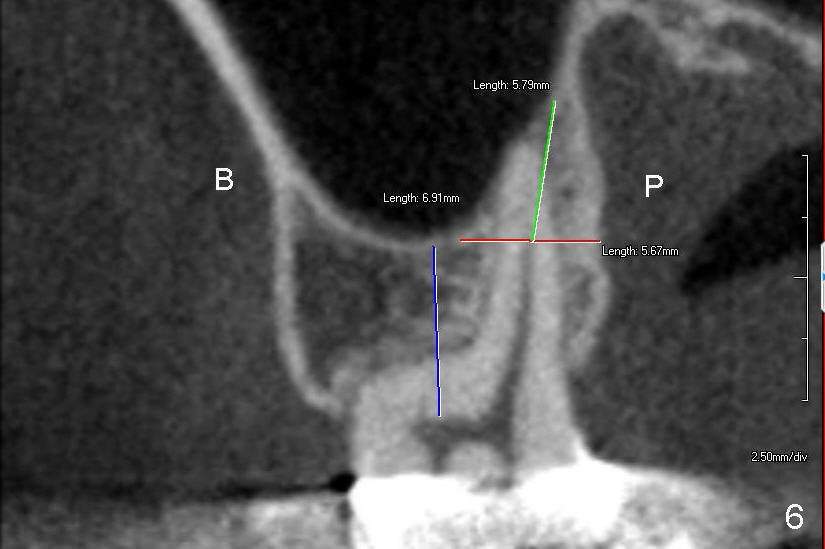

Prior to placement of 6x17 mm soft tissue level implant (Fig.1), the same size of tap is used. When the latter is removed, there is a small defect in the buccal wall of the osteotomy (mainly in the palatal socket) with the intact sinus membrane. There is no intraop or postop nasal hemorrhage. The patient returns for restoration 7 months postop; it appears that there is osteo-integration (Fig.2 with the mesial gap getting smaller (>)). The gingiva is healthy buccal (Fig.3: B) and palatal (Fig.4: P). The mesial gap is closed with formation of dense bone 4 years post cementation (Fig.7). Fig.5 is the preop PA of the patient, which shows that the palatal root (pink dashed line) is above the sinus floor and surrounded by the lamina dura. Fig.6 is a coronal section of the 2nd molar of another patient, which shows that the palatal root is 5-6 mm above the sinus floor. Upper Molar Immediate Implant Follow-Up Xin Wei, DDS, PhD, MS 1st edition 10/13/2013, last revision 05/18/2018